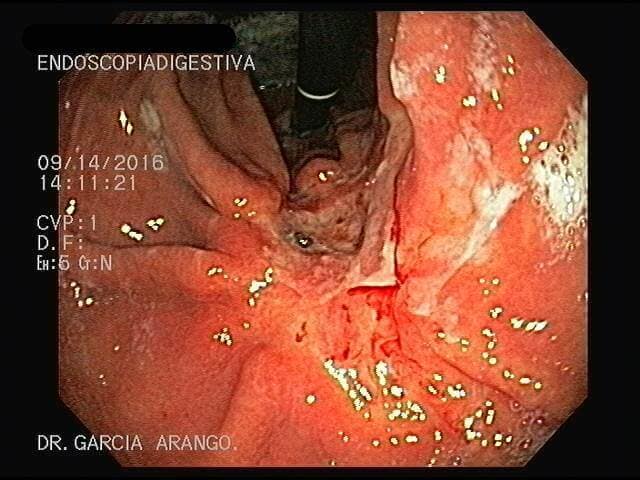

ENDOSCOPIA DIAGNÓSTICA Y TERAPÉUTICA AVANZADA CON ALTA DEFINICIÓN

⚕ Endoscopia de alta definición

⚕ Sangrado del tubo digestivo

⚕ Detección de cáncer de tubo digestivo

⚕ Videoendoscopia y biopsias